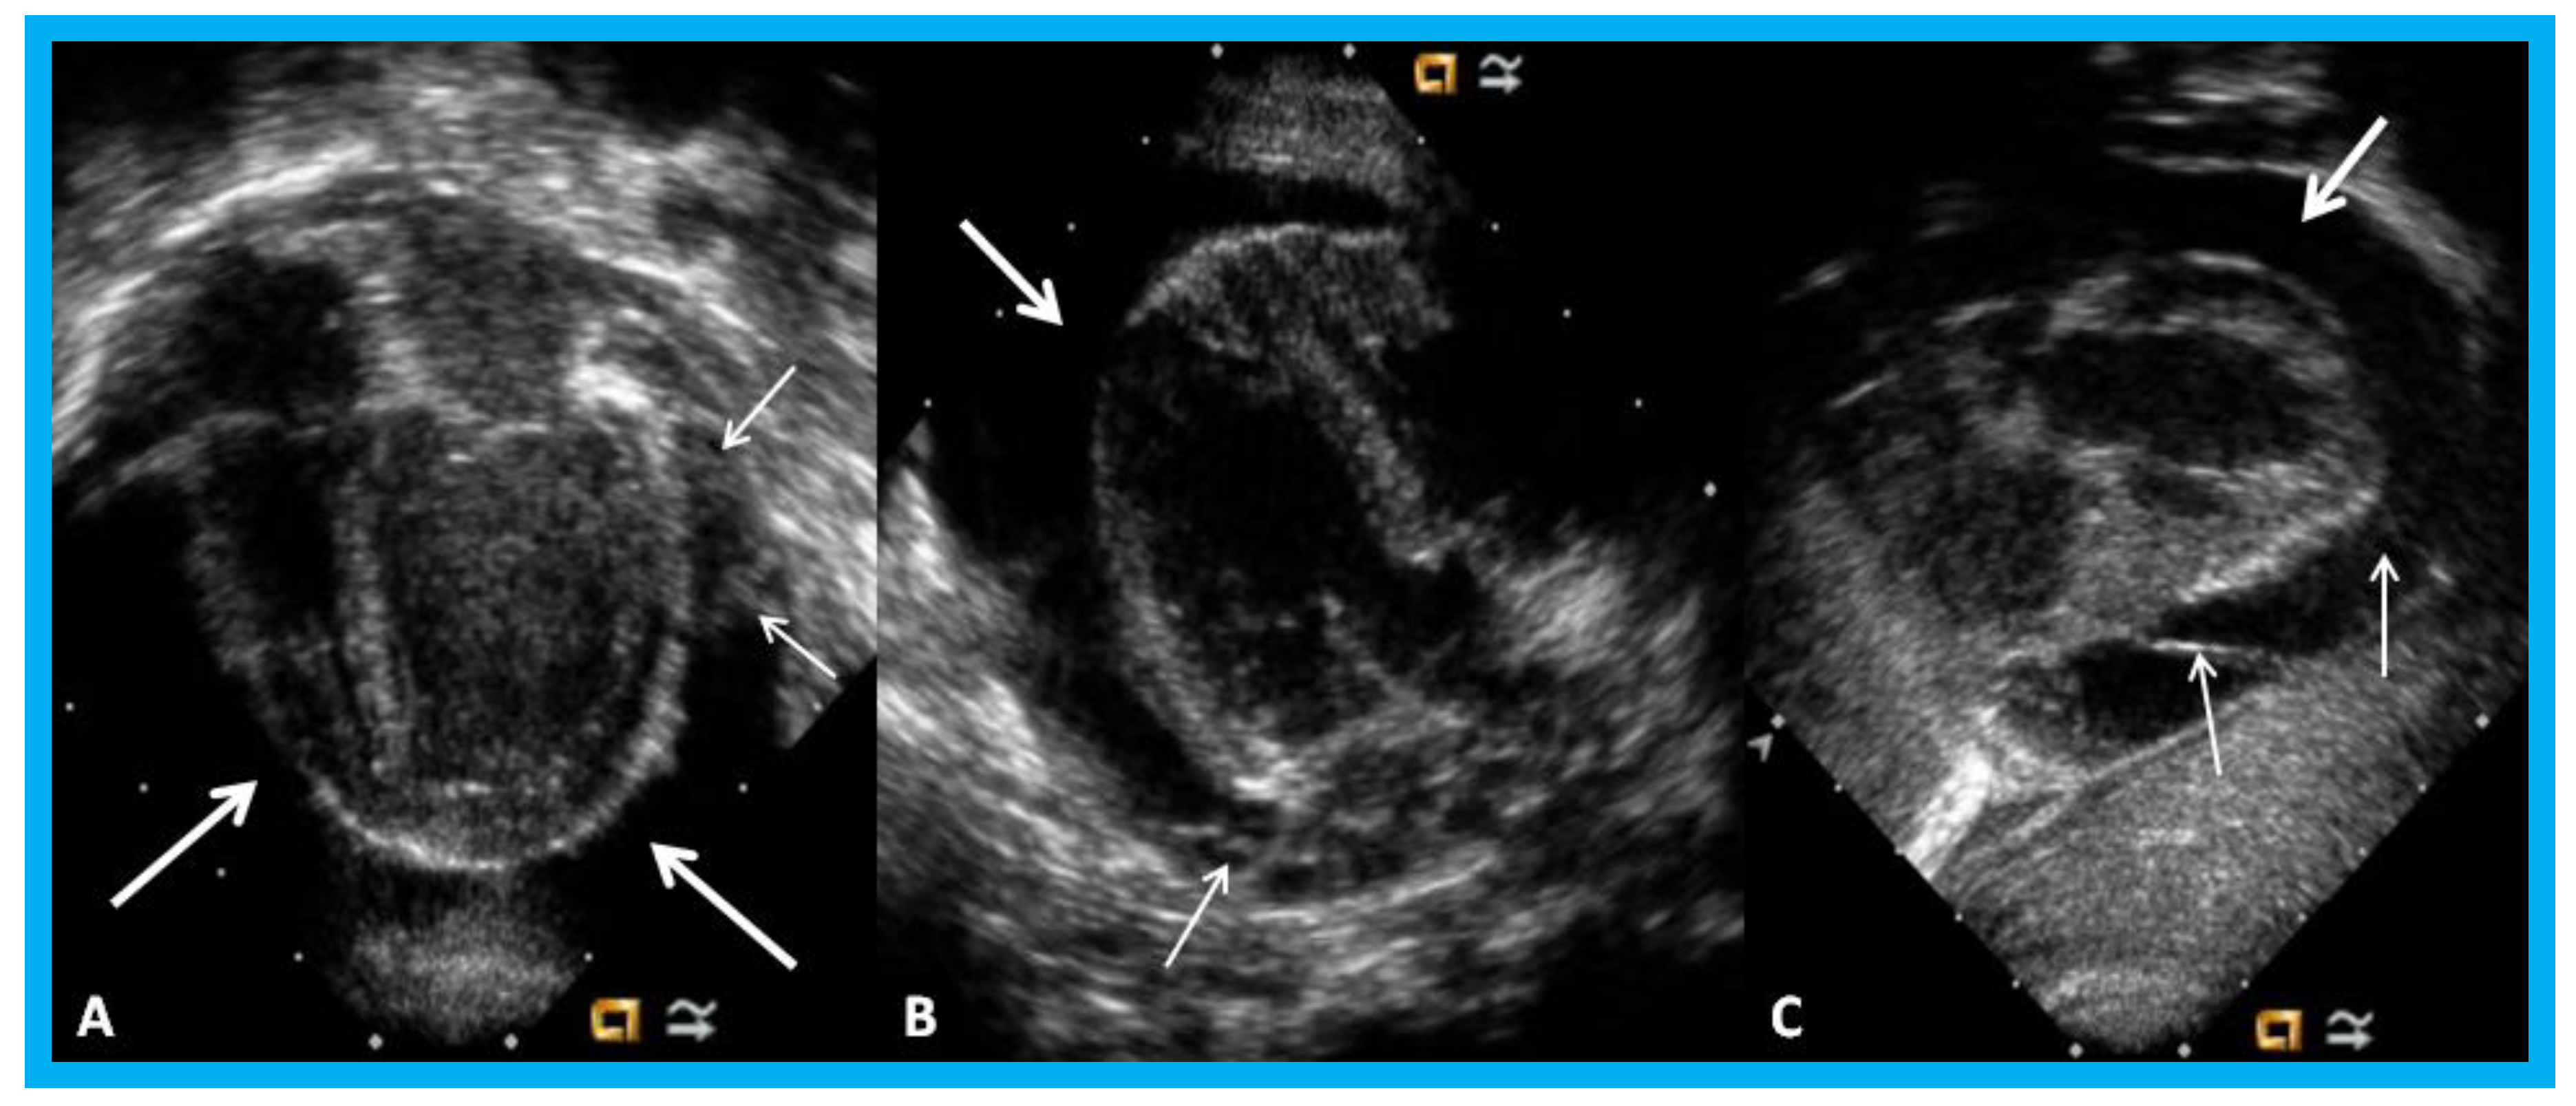

Figure 26. (A,B). Subcostal views of the left ventricle (LV) in an infant of a diabetic mother showing complete obliteration of the LV cavity in systole (arrow in (B)).

Figure 30. Apical four-chamber (A,B) and parasternal short axis (C) views of the heart in an infant with cardiomegaly showing a significant pericardial effusion (thick arrows): Fibrin strands in the effusion are shown (thin arrows).